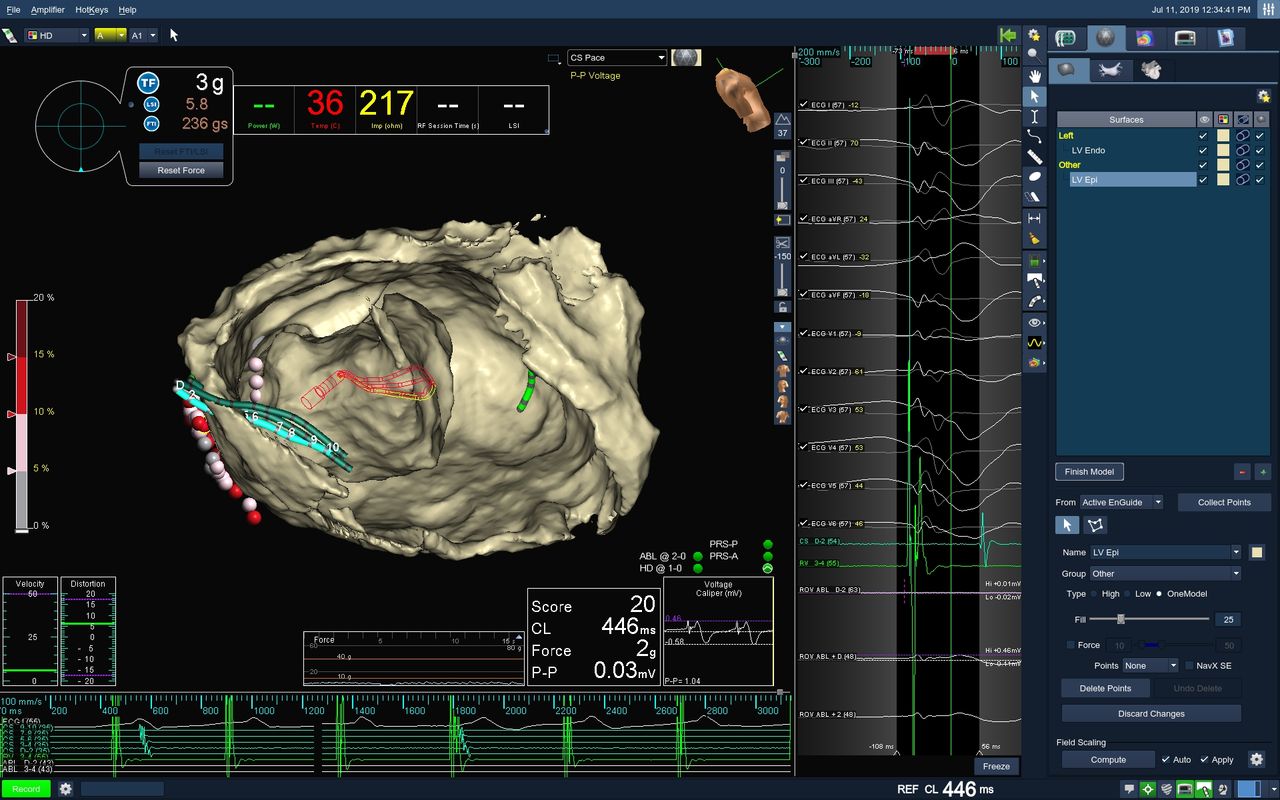

Realicé mi formación como médico general en la Universidad Autónoma de Veracruz Villa Rica, posteriormente la especialidad en medicina interna durante dos años en centro medico nacional Adolfo Ruiz Cortinez UMAE 14 en Veracruz, recibiendo en el primer año el reconocimiento por excelencia académica y en el segundo año reconocimiento al mejor promedio de mi generación. Realicé la subespecialidad en Cardiología clínica en el Centro Médico Nacional “La Raza”, en la Ciudad de México siendo jefe de residentes en el último año de la residencia médica, durante el tiempo la sede recibió el premio a la mejor cede de formadores de cardiología 2012-2013 premio otorgado por Dr. Enrique Graube (en ese entonces Director de medicina UNAM). Entre mis actividades asistenciales y conferencias, he presentado trabajos libres a nivel internacional (congreso de falla cardiaca lisboa 2013, Congreso mundial de cardiologia 2016, 2018 en AHA) ganador del premio internacional “la imagen más bella en cardiología, sociedad europea cardiologia España 2013”, así mismo presentación de más de 35 articulos publicados en revistas indexadas, soy miembro de la sociedad mexicana de cardiología no. 2076, asociación mexicana de cardiología, Fellow in training de la American collegue of cardiology capítulo México. Miembro de la sociedad europea de cardiología ESC ID 509395. Médico adscrito en el centro médico nacional la Raza, fui profesor adjunto del curso de cardiología en el mismo centro y sindal en el exámen de certificación de cardiología clínica de la sociedad mexicana de cardiología. Desde el 2016-2018 realicé curso de alta especialidad en electrofisiología cardiaca y estimulación cardiaca , realizando cursos fuera del país para especialización en técnicas avanzadas de ablación de arritmias, actualmente me encuentro realizando en el segundo año de la maestría en Dirección y Gestión de Instituciones de salud y Especialidad en Gestión de la Salud y Bienestar Corporativo

• Arritmias